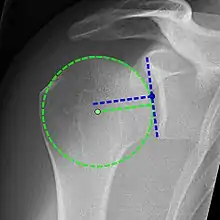

X-ray projectional radiography cannot directly reveal tears of the rotator cuff, a 'soft tissue', and consequently, normal X-rays cannot exclude a damaged cuff. However, indirect evidence of pathology may be seen in instances where one or more of the tendons has undergone degenerative calcification (calcific tendinitis). The humeral head may migrate upward (high-riding humeral head) secondary to tears of the infraspinatus, or combined tears of the supraspinatus and infraspinatus.[52] The migration can be measured by the distance between:

- A line crossing the center of a line between the superior and inferior rims of the glenoid articular surface (blue in image).

- The center of a "best-fit" circle positioned over the humeral articular surface (green in image)

Normally, the former is positioned inferiorly to the latter, and a reversal therefore indicates a rotator cuff tear.[52] Prolonged contact between a high-riding humeral head and the acromion above it may lead to X-ray findings of wear on the humeral head and acromion; secondary degenerative arthritis of the glenohumeral joint (the ball and socket joint of the shoulder), called cuff arthropathy, may follow.[51] Incidental X-ray findings of bone spurs at the adjacent acromioclavicular joint may show a bone spur growing from the outer edge of the clavicle downward toward the rotator cuff. Spurs may also be seen on the underside of the acromion, once thought to cause direct fraying of the rotator cuff from contact friction, a concept currently regarded as controversial.